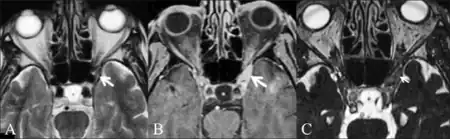

MRI scans of the brain and orbit with and without contrast, magnetic resonance angiography or digital subtraction angiography and a CT scan of the brain and orbit with and without contrast may all be useful in detecting inflammatory changes in the cavernous sinus, superior orbital fissure and/or orbital apex.[3] Inflammatory change of the orbit on cross sectional imaging in the absence of cranial nerve palsy is described by the more benign and general nomenclature of orbital pseudotumor.Sometimes a biopsy may need to be obtained to confirm the diagnosis, as it is useful in ruling out a neoplasm.[3] Other diagnoses to consider include craniopharyngioma, migraine and meningioma.[3]